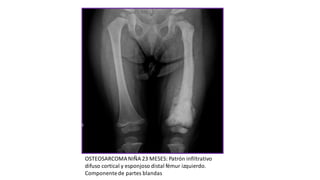

OSTEOSARCOMANIÑA 23 MESES: Patrón infiltrativo

difuso cortical y esponjoso distal fémur izquierdo.

Componentede partes blandas